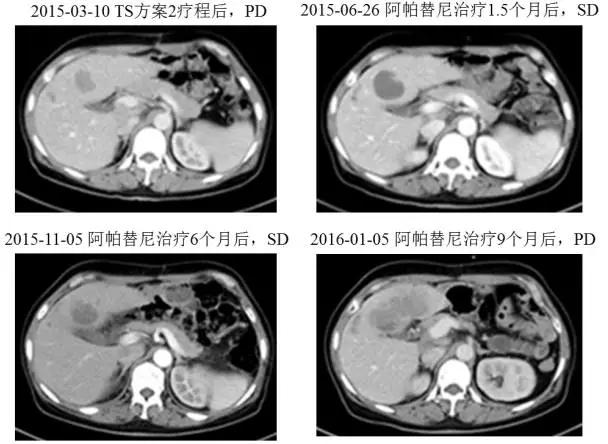

一线治疗对肿瘤控制情况不佳,于2015年4月改用阿帕替尼425mg poqd,3天后将剂量调整为850mg poqd。用药期间的不良反应主要为II度高血压,白细胞、血小板减少,I度腹泻,III度蛋白尿和双肩、膝关节疼痛。用药10天后,患者的AFP下降了37%,从56317降至35149ng/ml;1.5个月时AFP下降了74%,肝转移灶增大15%,CT值略降低,疗效评估为SD;3个月时AFP下降了75%,肝转移灶无变化,疗效评估为SD;6个月时AFP下降了84%,肝转移灶无变化,疗效评估仍为SD。

图3 患者阿帕替尼治疗前后的CT肝转移灶变化情况

患者于2015年11月开始出现大量蛋白尿(3-5g/24h),因此将阿帕替尼减量至425mg qd口服,但蛋白尿未见明显减少,遂停药2周(2015年12月17日至2016年1月5日),停药后蛋白尿降至0.72g/24h。2016年1月5日CT提示肝实质内大片状低密度病灶,较前增大110%。肠系膜区、腹膜后多发淋巴结,部分较前明显增大。AFP由7700升高至42000ng/ml。因此本次疗效评估为PD,二线阿帕替尼单药的TTP达到了9个月。